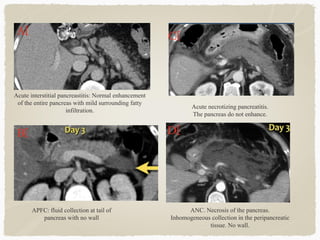

Acute interstitial pancreastitis: Normal enhancement

of the entire pancreas with mild surrounding fatty

infiltration.

ANC. Necrosis of the pancreas.

Inhomogeneous collection in the peripancreatic

tissue. No wall.

Acute necrotizing pancreatitis.

The pancreas do not enhance.

APFC: fluid collection at tail of

pancreas with no wall

Revised Atlanta Classification for Acute Pancreatitis 2012